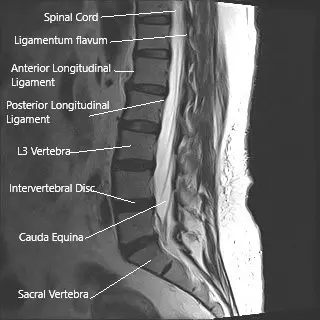

The spinal cord carries messages between the brain and the body. It runs through the spine and ends around the level of the first lumbar vertebra. Below this point, a bundle of nerves continues downward within the spinal canal—these are called the cauda equina because they resemble a horse’s tail.

These nerves control sensation and movement in the legs, bladder, bowel, and sexual organs. Because they are exposed within the canal and not protected by bone or tissue as strongly as the spinal cord, they are more sensitive to pressure or injury.

MRI of the lumbar spine in sagittal section showing cauda equina (horse’s tail)